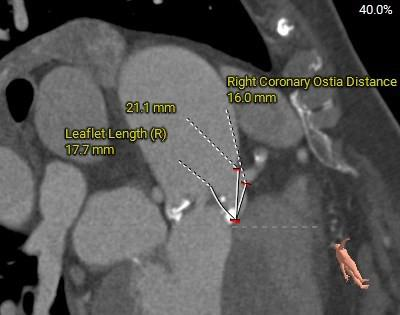

左室大小及冠脉阻挡风险

◇ 左右冠高度可,左侧冠脉切线位瓣叶长度<左侧冠脉开口上缘到瓣叶附着缘距离长度<右侧冠脉开口上缘到瓣叶附着缘距离,左冠回旋支及右冠有钙化分布,结合瓦式窦及STJ预估冠脉阻挡风险较低;